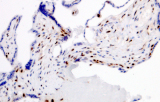

Apoyo al diagnóstico diferencial

Los paneles de IHQ permiten diferenciar entre mimetizadores benignos, tumores GU primarios y malignidades metastásicas mediante el resaltado de linaje celular y antígenos tumorales específicos.